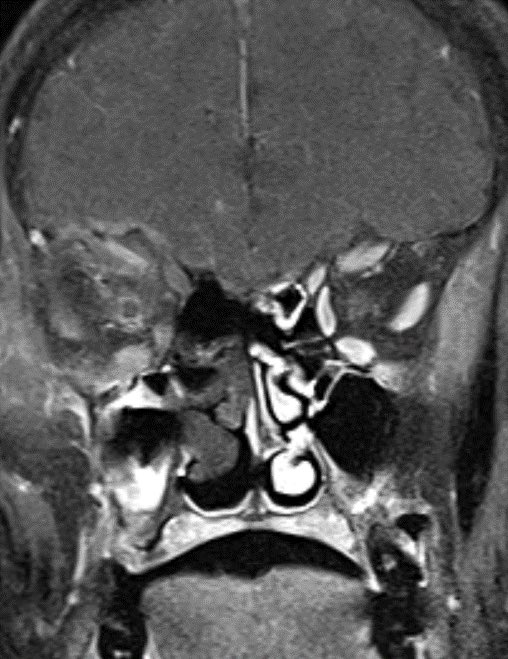

60 y/o with history of diabetes presents with progressive right proptosis, vision loss and confusion. What is the most likely diagnosis? 🧠

💡 Black Turbinate Sign has been reported as a finding highly suggestive of invasive fungal rhinosinusitis in immunocompromised patients

💡 Absent sinus mucosal enhancement is a 🔑 imaging feature as it implies invasion with vascular compromise and necrosis of the mucosa

The black turbinate sign is very specific in the appropriate setting though often not seen

💡 We must look for extra sinus invasion, particular intracranially, intraorbital, retromaxillary and other areas of absent mucosal enhancement to aid in the diagnosis

💡Benign turbinate nonenhancement can occur, look for:

1️⃣IMMUNOCOMPETENT host without clinical suspicion

2️⃣Improves over subsequent series

3️⃣Has preserved thin peripheral enhancement

4️⃣Often has thin internal septa

5️⃣Often occurs in the posterior aspect of the inferior turbinate